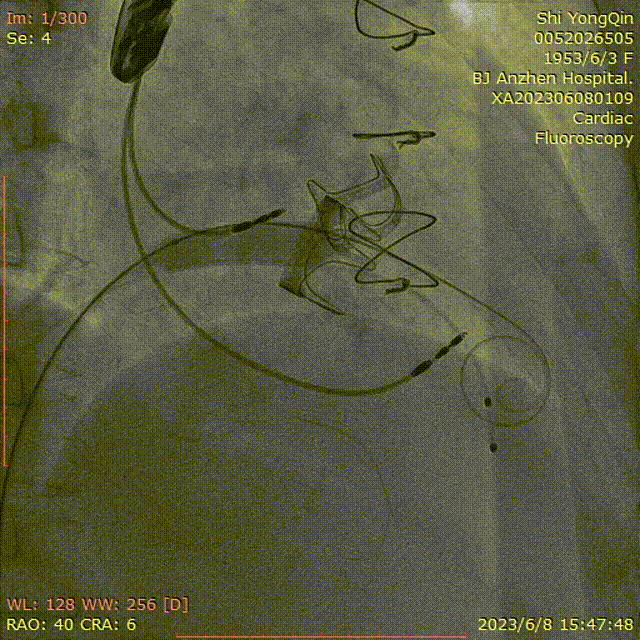

患者全麻,摆体位可寻找衰败生物瓣的切线投照体位,后消毒铺巾,穿刺双侧股静脉,左侧股静脉植入临时起搏器,右侧股静脉作为主入路,在超声指引下,按术前CT评估要求穿刺房间隔到达左心房,肝素化后(ACT>250秒),导入Agilis可调弯鞘管到达左心房,Pig造影导管跨过二尖瓣到达左心室心尖部,导入Safari导丝到达左心室;以12×40mm球囊扩张房间隔确认SAPIEN 3瓣膜可通过后,导入反向安装的23mm+3ml瓣膜到达下腔静脉,组装成功后,翻转其调弯系统后送入到左心房,跨过衰败的二尖瓣,在切线投照体位定位精确后,快速心室起搏下释放瓣膜,见瓣膜位置良好,超声显示无瓣周漏,测量左心室和桡动脉压差稍增高,超声显示LVOT流速稍增快;撤出瓣膜输送系统及导丝,撤出临时起搏电极,局部加压包扎,患者清醒后安返病房。

瓣膜导入

瓣膜的定位及释放

术后超声评估无反流